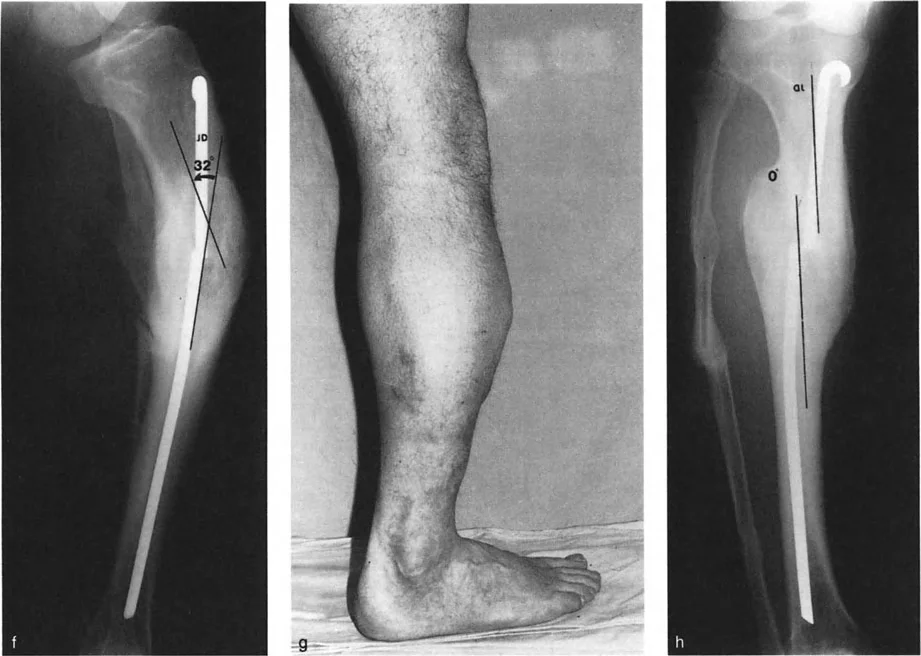

تشوهات المستوى التشريحي والمائل بزاوية أقل من 90 درجة

في هذا النوع، يمكن رؤية الانحراف والانزياح معًا في إحدى الأشعة السينية (الأمامية الخلفية أو الجانبية)، بينما يظهر في الأخرى أحد المكونين فقط (إما انحراف أو انزياح). هذا يعني أن أحد مكوني التشوه (الانحراف أو الانزياح) يقع في مستوى مائل، بينما المكون الآخر يقع في مستوى تشريحي. عندما يتم رسم هذه المستويات بيانيًا، تكون مختلفة ولكن بزاوية أقل من 90 درجة.

مثال: التئام خاطئ لعظم الساق الأيسر حيث يظهر الانحراف والانزياح في الأشعة السينية الأمامية الخلفية (AP)، بينما يظهر الانزياح فقط في الأشعة السينية الجانبية (LAT). أو قد يظهر الانحراف فقط في LAT.

في هذه الحالات، إذا كان الانحراف هو المكون التشريحي، فإن مركز دوران الانحراف (CORA) سيظهر إما قريبًا أو بعيدًا عن الالتئام الخاطئ في الأشعة السينية الأمامية الخلفية (AP) أو الجانبية (LAT). أما إذا كان الانحراف هو المكون المائل، فسيظهر مركز دوران الانحراف (CORA) قريبًا أو بعيدًا عن الكسر في المنظر الذي يظهر أقصى انزياح، وعند مستوى الكسر في المنظر الذي لا يظهر فيه انزياح.